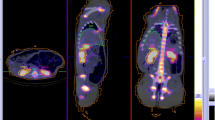

Absorbed doses to salivary and lacrimal glands following [177Lu]Lu-PSMA therapy are summarised in Appendix 1, Table 6, and images acquired prior to, and during therapy with [177Lu]Lu-PSMA are shown in Fig. 4. As with other tissues, a large inter-patient variability is observed. For salivary glands, the absorbed doses range between 0.5 and 1.9 Gy/GBq. Studies that included dosimetry for more than one cycle demonstrated a modest variation between cycles [12, 23]. For lacrimal glands, the absorbed doses range between 0.4 and 3.8 Gy/GBq. One study reported a mean absorbed dose of 16 ± 4 Gy per therapy cycle, each of 5.5 GBq [177Lu]Lu-PSMA-617, which was almost 4 times higher than the absorbed dose to the salivary glands [67]. The lacrimal glands can potentially be considered the main organ at risk in therapy with 177Lu-PSMA, although presently, no significant concern of xerophthalmia has been reported [23].

The pituitary gland has a high expression of SSRs (Fig. 5). Absorbed doses to the pituitary gland following [177Lu]Lu-SSRT therapy have been investigated by planar image quantification with reported mean absorbed doses of 0.89 Gy/GBq (range 0.46–1.8 Gy/GBq) [69]. Radiobiological modelling was used to compare tolerance levels derived from EBRT, arriving at an EQD2 of 3.5 Gy (1.7–7.7 Gy) per 7.4 GBq cycle.